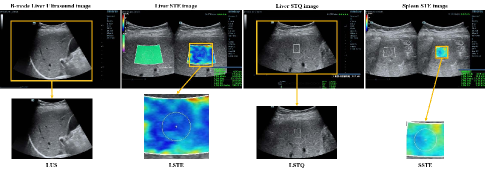

A dataset consisting of four modalities is constructed in this work. They were collected in the clinical examination of liver fibrosis, named by liver STE images (LSTE), spleen STE images (SSTE), liver STQ images (LSTQ) and liver ultrasound images (LUS), as illustrated in Fig. 2.

In the clinical examination of one patient, the doctor collected seven US images, five LSTE images, three to five LSTQ images and three to five SSTE images that reflect liver fibrosis to a certain extent. In addition, the doctor collected ultrasound videos from some patients. By video sampling, we obtain 2030 more LUS images for each patient with video data. The illustration of these four kinds of images was shown in the first line of Fig. 2. The regions inside the yellow box are taken as the final inputs.

Refer to caption

Fig. 2: Dataset illustration.

We first implemented mono-modal experiments using the ResNet-50 based neural network to investigate how each modal is performed. The input images of each modal were illustrated in the second row of Fig. 2. For LSTQ and LUS, the complete LUS image was selected. For LSTE (or SSTE), the square with the size of 224×\times224 pixels including the entire ROI was selected as the input. For evaluation, 80%percent8080\% of the patients in each stage was selected to constitute the training dataset and the rest for testing.